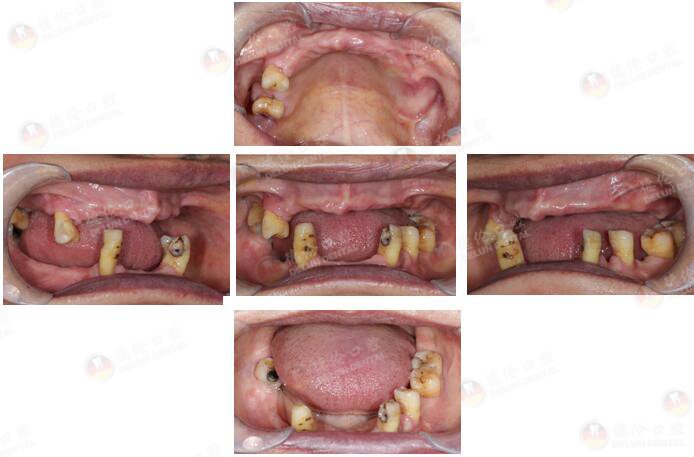

许女士 65岁

牙齿症状:全口多牙缺失十余年。

10余年前因牙周炎致全口多牙拔除,之后利用活动假牙修复,现在出现活动假牙固位差、牙龈游走性压痛等情况,希望做种植牙修复。